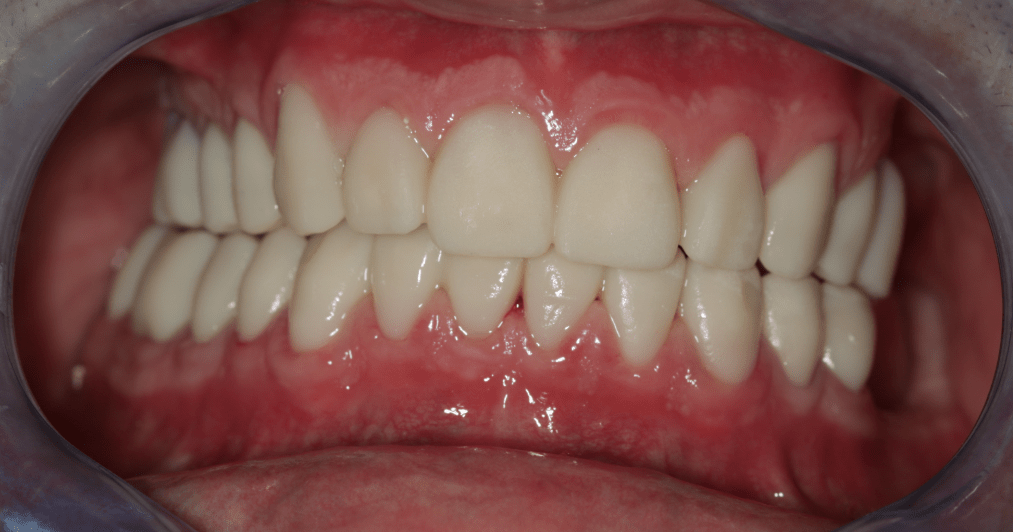

Ezek segítségével a fogtechnikai laboratórium elkészített egy hosszú távú, ideiglenes pótlást, amelyet a páciens 3 hónapon át hordott, természetesen szoros nyomon követés, kontrollok mellett. Ennyi idő alatt a páciens panaszai nagyrészt meg is oldódtak.

Miután a pácienssel megbizonyosodtunk a pótlás funkcionalitásának sikerességéről, készre kértük a fogtechnikai laborból azt a cirkóniumpótlást, amely a kisebb korrekciókon átesett ideiglenes pótlás tökéletesen pontos mása lett.

A páciens az elért eredménnyel mind funkcionálisan, mind esztétikailag azóta is maximálisan elégedett.